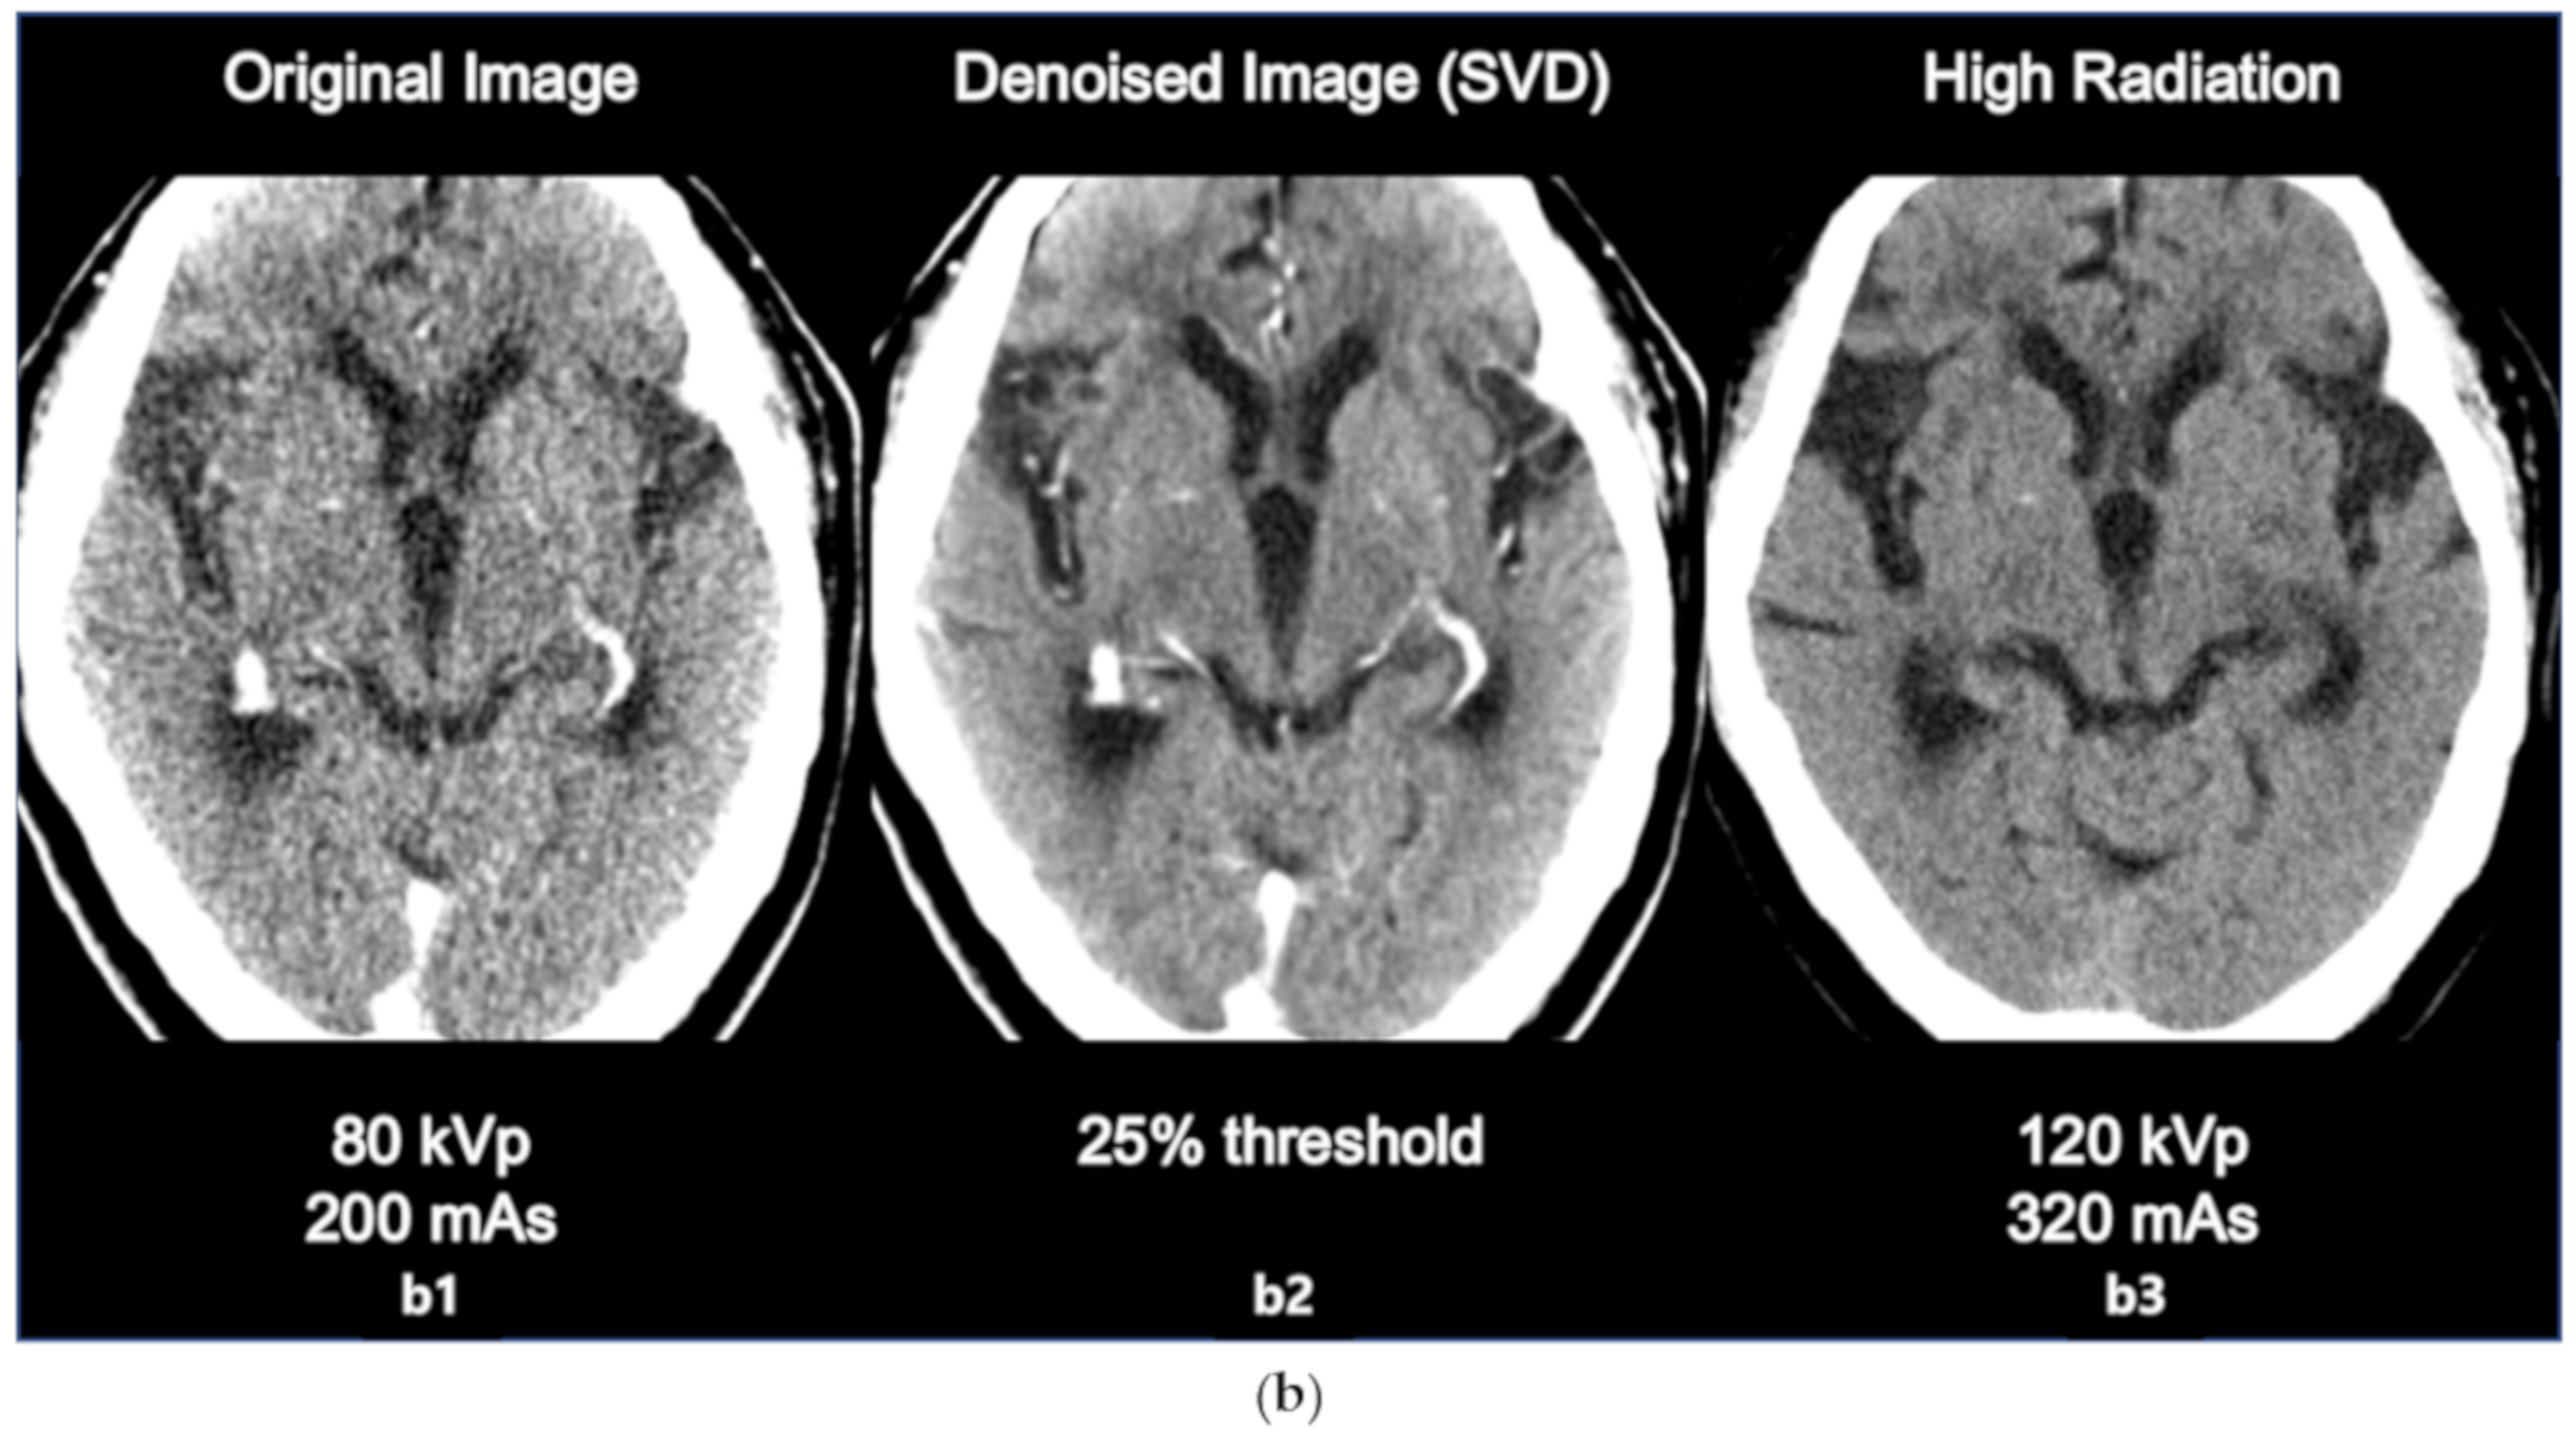

3.2. Comparison with High Radiation Dose Image

The comparison between original image, denoised image, and high radiation dose image is as in the following Figure 4a,b. The sharpness of ventricle and parenchyma margin, the distinctness of basal ganglia and parenchyma in the denoised image, and the differentiation of gray matter and white matter in the denoised image was clearly described close to original high dose image.

Figure 4.

(a) Comparison between the original image (80 kVp, 200 mAs, a1 the denoised image using SVD (25% threshold, a2, and the high dose image (120 kVp, 320 mAs, a3). (b) Comparison between the original image (80 kVp, 200 mAs, b1), the denoised image using SVD (25% threshold, b2), and the high dose image (120 kVp, 320 mAs, b3).

The results of the SNR and CNR estimations are presented in Figure 5a,b. In Figure 5a, the mean SNRs at the basal ganglia level exhibited a significant increasing tendency except for the 15% and 30% threshold values. The largest improvement involving a significant 16% increase (t = 2.908, p < 0.005) was observed at the 40% threshold setting. Similarly, in Figure 5b, the mean CNRs at the basal ganglia level maintained an increasing tendency for every threshold setting. The largest improvement involving a significant 43% increase (t = 6.327, p < 0.001) was also observed at the 40% threshold setting. However, image a6 that is labeled as 25% of the threshold value resulted in the best statistical significance per the results of the paired t test (t = 3.764, p < 0.001), resulting in an adequate 14% increase in the SNR. Considering the example dataset presented in Figure 3a, even though the 40% setting resulted in the highest SNR, the 25% setting appeared to generate more diagnostic information associated with the vessels. The 25% setting also resulted in good CNR estimation results with a statistically significant 37% increase (t = 6.080, p < 0.001). Based on these findings, we considered that the 25% setting could potentially be the optimal setting for 4D axial CTP images at the basal ganglia level in terms of compromising between noise reduction and preserving diagnostic information. In addition, we would like to highlight that we were able to achieve a considerable improvement in quantitative image quality in the denoised images without having to increase the radiation dose. Figure 4a,b shows the comparison of the original image with the lower dose image (80 kVp, 200 mAs, a1), the denoised image (80 kVp, 200 mAs, 25% of threshold, a2), and the higher dose image (120 kVp, 320 mAs, a3). Regarding Figure 4a,b, we would like to believe that we were able to improve the diagnostic value of low dose (Figure 4a,b, a2, b2) image similar to the ones scanned with high dose (Figure 4a,b, a3, b3) by using the proposed SVD-denoising technique. In other words, there is potential to preserve sufficient image quality even in scans involving lower tube currents. Lowering the tube current and tube voltage is the simplest way to reduce the radiation dose involved in a CT scan. Based on the fact that the amount of noise on an image is inversely proportional to the square root of the radiation dose, reducing tube current and tube voltage can inevitably lead to the degradation of image quality, thereby generating a larger amount of noise on the image [30,31]. Considering this, additional studies to investigate the qualitative and quantitative comparison between the denoised lower dose image and higher dose image on CTP may be meaningful. Additionally, further study with artificial biological objects using 3D bioprinting will be required for more accurate evaluation.